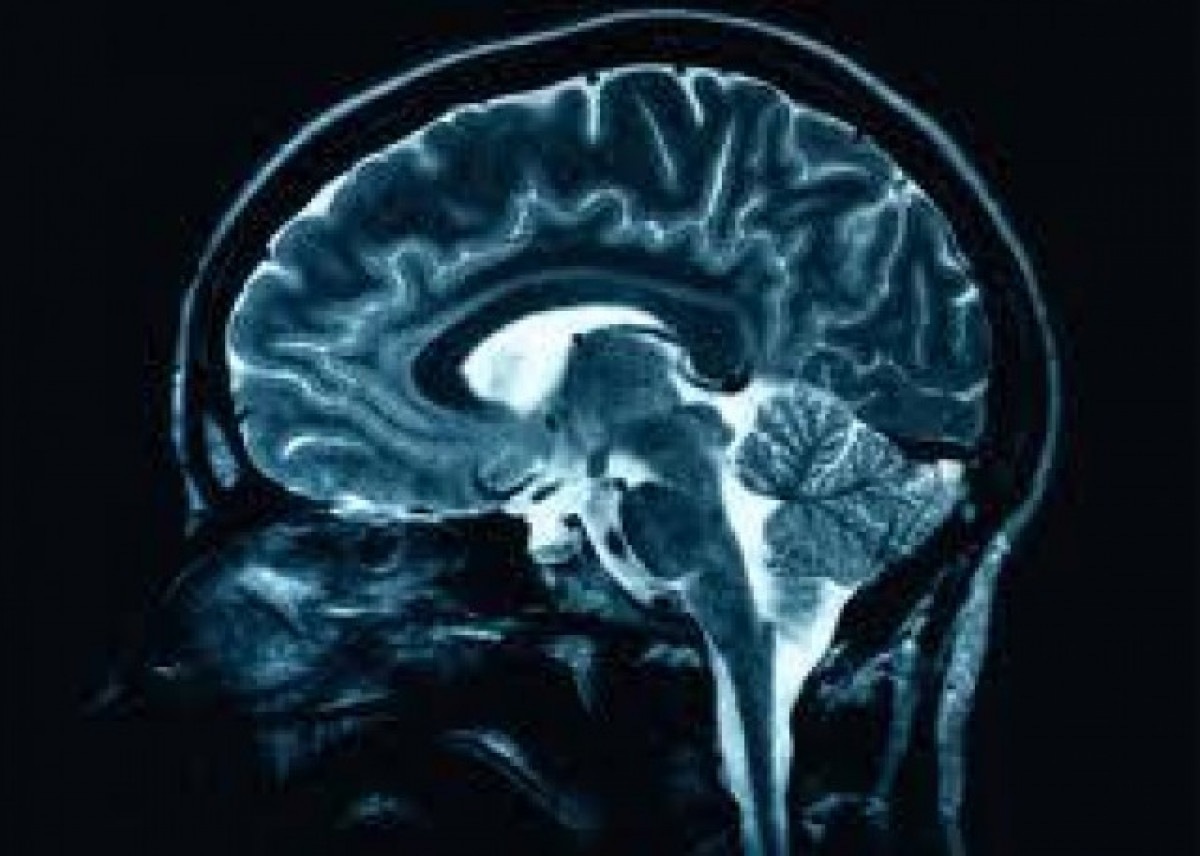

Aconsegueixen per primera vegada portar fàrmacs fins al centre d'un tumor cerebral

Un equip del Centre d'Investigació en Medicina Molecular i Malalties Cròniques (CiMUS) de la Universitat de Santiago de Compostel·la ha creat unes nanopartícules capaços de penetrar un tumor cerebral i transportar fàrmacs genètics a l'interior de les seves cèl·lules malignes.

La tècnica, desenvolupada pel grup dirigit per l'investigador Marc García Fonts en col·laboració amb l'Institut de Salut Carlos III i la Universitat de Nottigham, "està cridada a millorar la situació dels malalts del tumor cerebral més comú i letal", la taxa de supervivència als cinc anys "és menor del 5%".